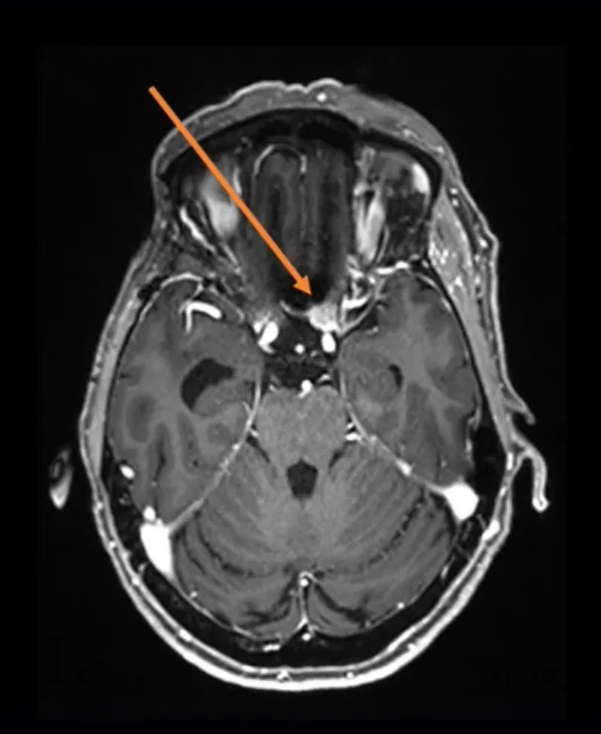

简要病史:2005年,75岁的法国女士因右侧海绵窦脑膜瘤进行了一次开颅手术。2016年,左侧视力进行性下降,检查视力结果左侧视力4.6(右侧5.0),左侧视神经管内侧病变均匀增强,还报告翼点空化是由颞肌萎缩引起的。诊断确定脑膜瘤位于视神经管的中下侧(图1),导致了视力严重恶化。

图1:术前MRI